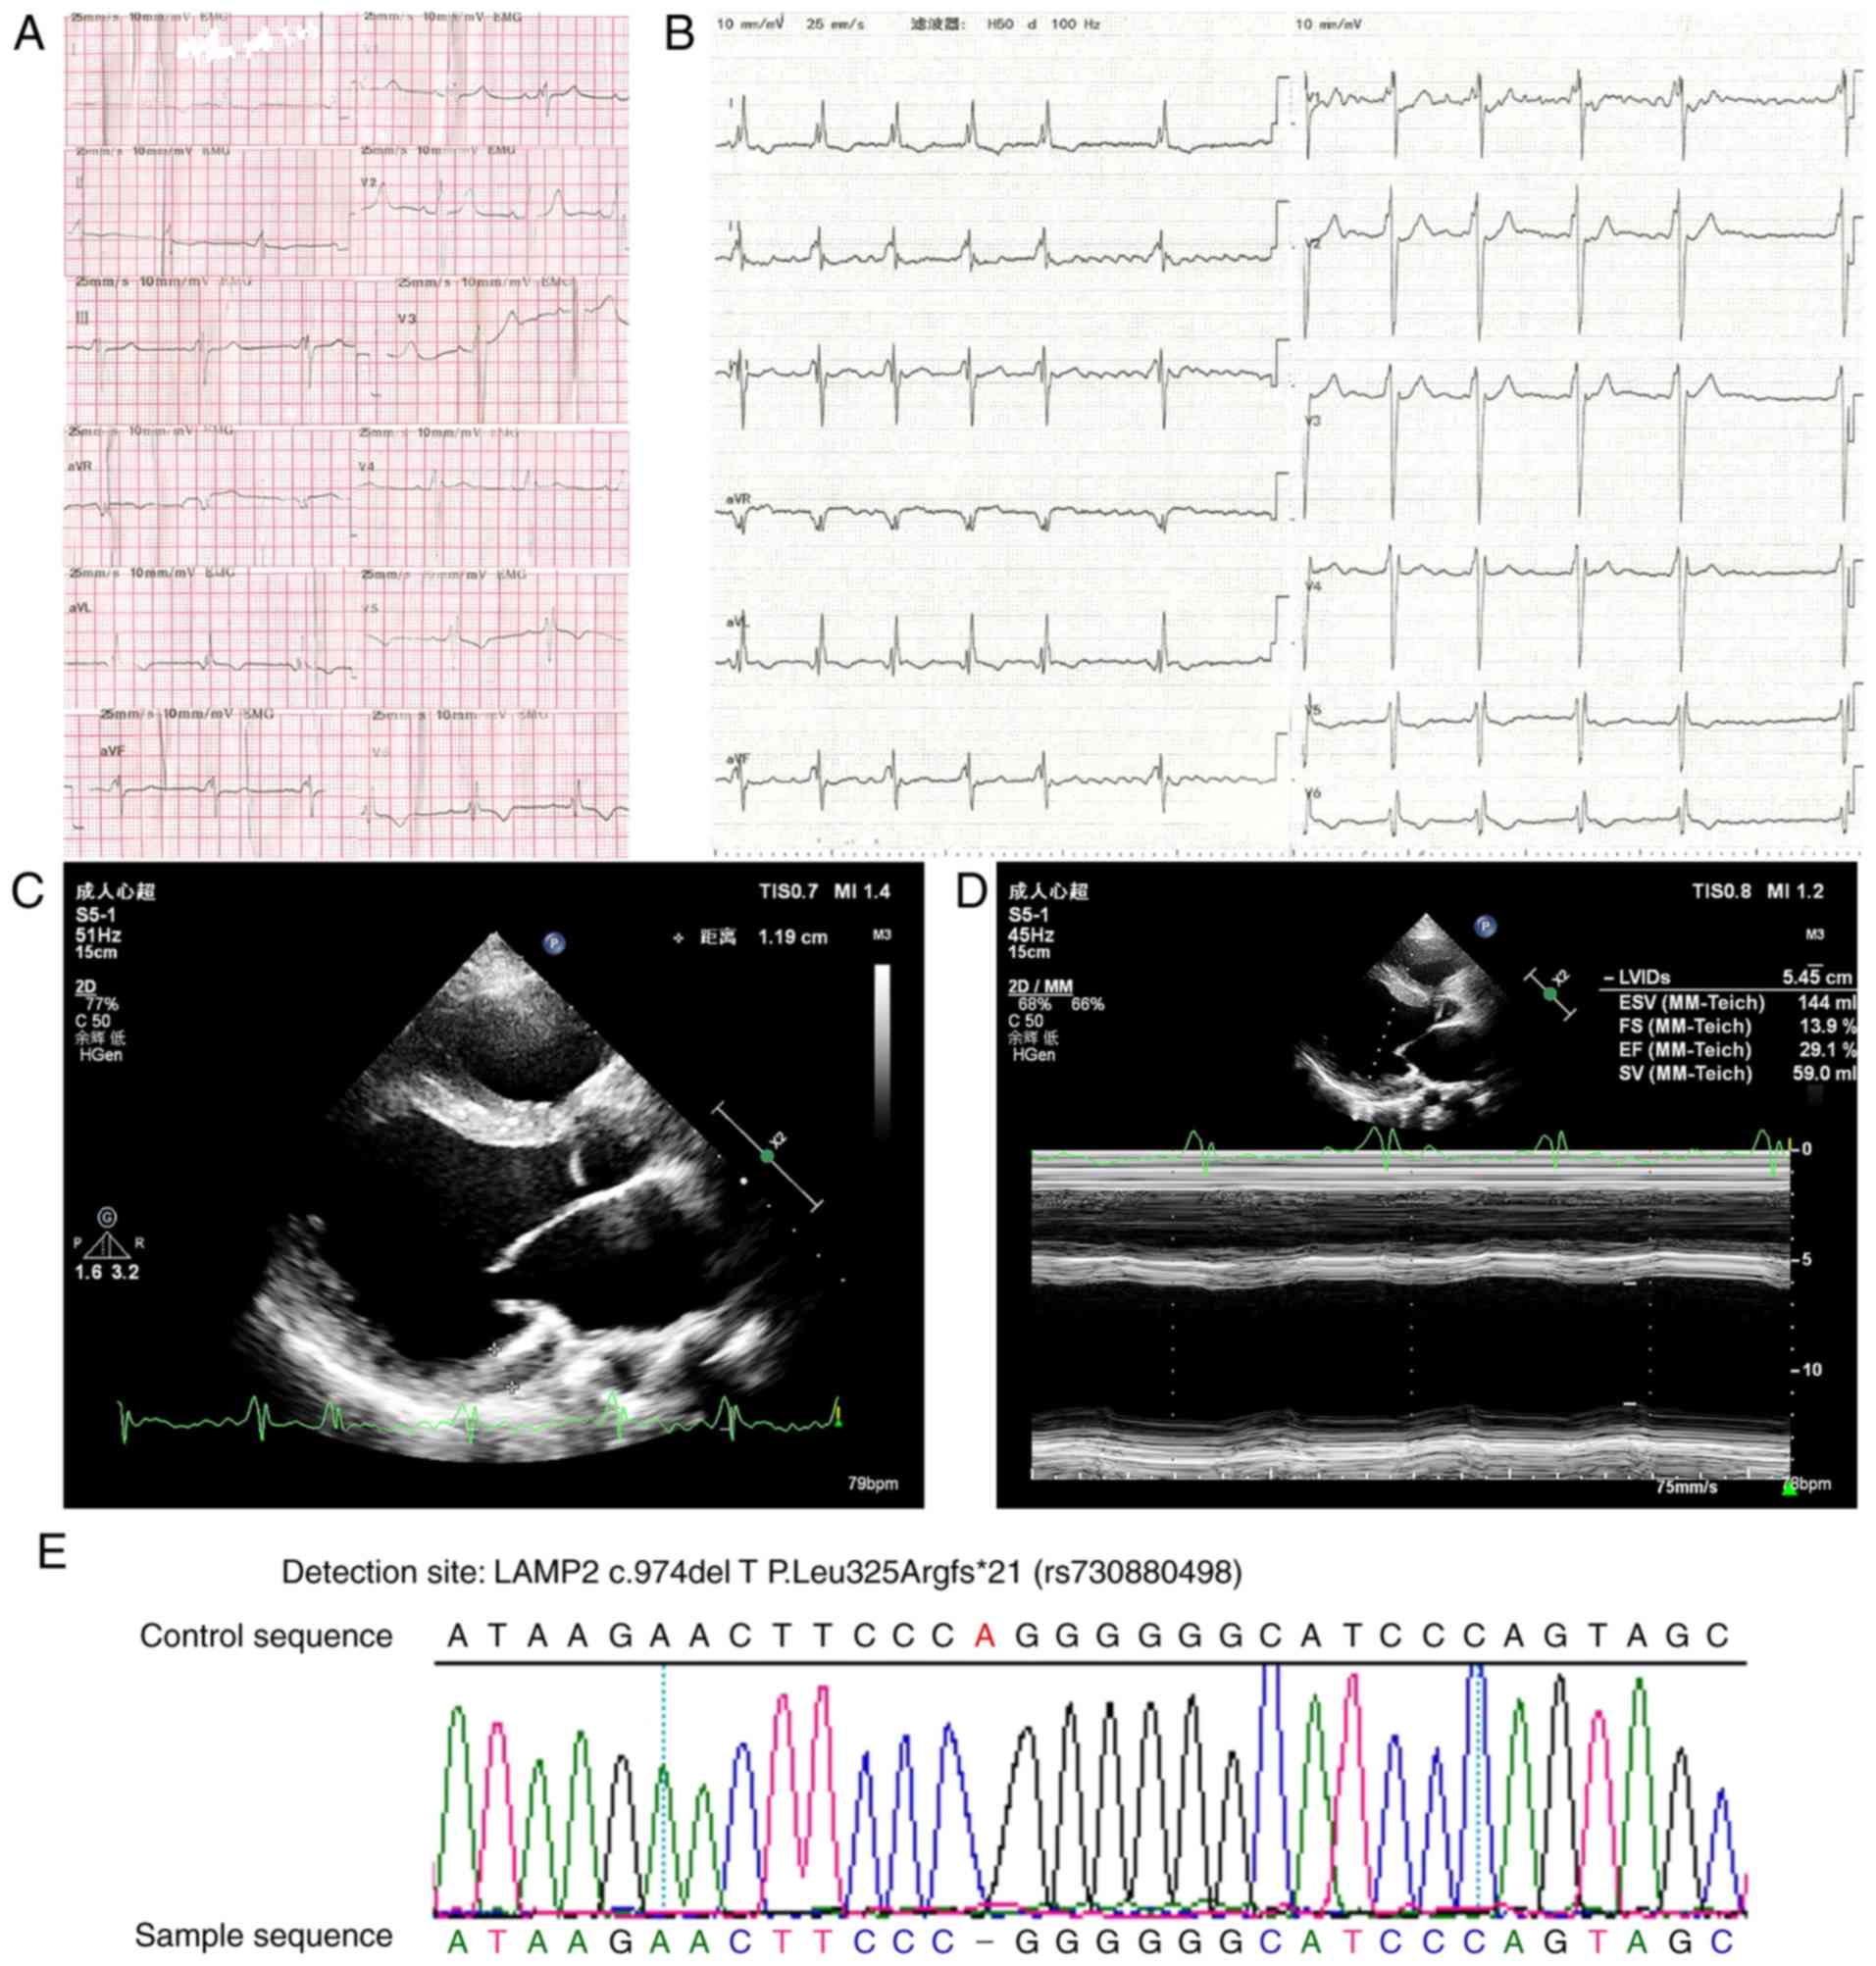

electrocardiogram (ECG) exhibited a ventricular pre-excitation

pattern at the first hospitalization (Fig. 2A). At nine months later, the patient

was admitted due to advanced heart failure with persistent AF

(Fig. 2B). The echocardiographic

examination revealed mild left ventricular hypertrophy

(interventricular septum, 13 mm; left ventricle anterior wall, 12

mm) and dilated left heart (atrium, 37 mm; left ventricle at end

diastole, 63 mm) (Fig. 2C). The left

ventricular systolic function was severely impaired with an

ejection fraction of 29% (Fig.

2D).

Biopsy specimens were taken from the patient's left

deltoid muscle. NADH enzyme staining indicated that small irregular

vacuoles were scattered in certain muscle fibers, and a small

amount of type I muscle fiber aggregated in edge particles

(Fig. 3C). ATPase staining revealed

clustering in some areas (Fig. 3B).

The pathological diagnosis was myogenic fiber disorder myopathy

(Fig. 3).

For sequence analysis, DNA was extracted from blood.

A heterozygous frameshift missing mutation was identified in the

LAMP2 gene of the patient. The proband harbored an identical

c.974delTinsAA in exon 8 (Fig.

2E).